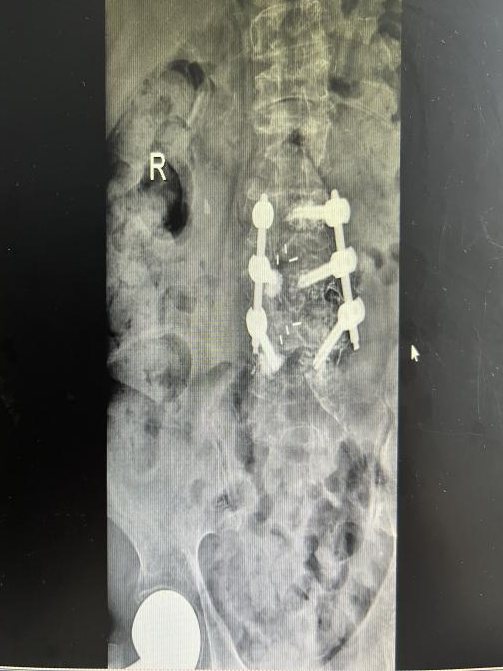

为提升区域内基层医疗机构糖尿病足诊疗服务能力、促进青年医师对糖尿病足的规范化诊治水平,遵义市第二城市医疗集团总院(贵州航天医院)圆满举办贵州省继续医学教育项目——胫骨横向骨搬移技术治疗糖尿病足专题研讨班。 贵州航天医院党委委员、副院长彭亮出席会议并致辞,遵义市第二城市医疗集团各成员单位,以及红花岗区、汇川区、绥阳县、桐梓县等多个区县的基层医疗机构骨干医师参加会议。 研讨班 本次研讨班以胫骨横向骨搬移技术在糖尿病足治疗中的应用为核心主题,围绕糖尿病药物治疗与生活方式管理策略、围手术期血糖精准调控要点、胫骨横向骨搬移技术典型病例深度解析、糖尿病足的临床分型与个体化治疗方案制定等临床实践中的热点与难点展开深入探讨,通过专题授课、案例研讨、互动交流等多元化形式,为参会者搭建了理论与实践结合的学习平台。 此次研讨班不仅为区域内基层医院搭建了学术交流与经验共享的平台,更对推动糖尿病足预防、诊断与治疗的规范化、系统化发展起到了积极作用,有效助力青年医师更新专业知识体系、提升临床技能,为进一步保障区域内糖尿病足患者的健康奠定了坚实基础。 贵州航天医院骨科专家简介 陈明勇 骨一科主任,副主任医师 临床擅长:从事创伤骨科工作约20年,对骨缺损、骨不连、骨肿瘤、肢体畸形等的肢体矫形重建及功能重建,慢性化脓性骨髓炎的根治治疗、糖尿病足的保肢治疗、快速康复理念(ERAS)下的老年骨折的诊治,四肢复杂骨折的诊治,四肢骨折等微创手术治疗具有丰富的临床经验。 2004年毕业于遵义医学院临床专业,曾在中国人民解放军总医院、广西医科大学第一附属医院、上海第六人民医院骨科进修。中国中西医结合学会骨伤科专业委员会横向骨搬移治疗糖尿病足及微血管网再生学组首届委员,遵义市医学会创伤分会常务委员。 瞿 晖 骨科党支部书记,骨二科主任,副主任医师 临床擅长:对骨科的常见病、关节外科、脊柱外科及运动医学疾病的诊治具有丰富的临床经验,熟练掌握骨科手术操作技术。 毕业于遵义医学院临床医学系,2005年前往广州中山大学第一附院骨显微医学部进修学习,2011年前往成都华西医院进修学习,并多次在省内外学习骨科相关知识,是中华医学会骨科分会会员。 赵小锋 中共党员,骨二科副主任,副主任医师 临床擅长:从事骨科临床工作11年,对骨科常见病、多发病诊疗有较为丰富的临床经验,擅长脊柱相关疾病诊断及治疗,尤其是颈、腰、腿疼痛疾病诊断及治疗,擅长胸腰椎骨折微创经皮穿刺内固定术、经皮穿刺椎体成形术、经皮穿刺脊柱内镜下腰椎间盘摘除术、单纯开创腰椎间盘摘除术、腰椎滑脱复位椎间植骨椎融合内固定术、腰椎管狭窄减压融合内固定术及人工髋、膝关节置换术等。 2012年毕业于遵义医学院外科学专业硕士研究生,2019年参加“遵义市115医学人才精英计划”于上海交通大学第一附属医院培训学习,2023年于北京大学第三人民医院脊柱外科进修学习,曾获得遵义市优秀医师荣誉称号。 遵义市手外科第一届委员,遵义市医学会创伤分会第一届委员,遵义市医学会创伤分会第二届委员,贵州省康复医学会第三届脊柱脊髓专业会委员,遵义市医学会烧伤与整形外科学分会委员,发表论文5篇,其中国家级核心期刊1篇,SCI论文1篇,主持市级课题1项并结题,参与市级课题2项。 赵兴东 骨科主任医师 临床擅长:擅长骨科的常见病及各种创伤、四肢骨折创伤修复、骨感染、手足疾病的诊治和手足体表畸形的矫形整复,熟练掌握骨科四肢骨病及创伤的手术操作技术,尤其在四肢关节复杂性损伤、手足外伤、组织缺损创面、难治创面的皮瓣修复方面及平足、高弓足矫形方面及四肢慢性疼痛诊治、康复方面具有丰富的临床经验。 硕士研究生,毕业于遵义医学院临床外科系,2015年前往山东省立医院手足外科进修学习;遵义市医学分会创伤分会第一、二届委员,遵义市手外科医学会第二委届员会常务委员;在省级及省级以上期刊发表文章9篇,参编著作2部,参与主持并完成市级课题1项,参与市级课题2项、省级课题1项。 张艳金 中共党员,骨科副主任医师 临床擅长:从事骨外科工作16年,对复合伤、多发伤的救治、四肢骨干骨折、关节周围骨折、骨肿瘤、骨髓炎等诊治具有丰富的临床经验。 中共党员,硕士研究生,2006年本科毕业于山西医科大学第二临床医学院,2011年研究生毕业于北京军区总医院;在“老年COPD患者合并髋部骨折的诊治”国际合作课题组研究两年,在老年髋部骨折的诊治方面具有丰富的经验,并发表论文6篇;主持遵义市级课题1项,承担遵义医科大学的临床教学工作,获得遵义医科大学优秀带教老师荣誉。编撰有《骨科疾病诊疗精粹》一书,开展2项新技术,编撰地方规范《务川自治县创伤骨科常见疾病诊疗规范》一书。 张俊凯 骨科副主任医师 临床擅长:从事骨科临床工作28年,对创伤骨折、骨感染、骨缺损、骨不连等外科诊治,四肢骨折的微创手术治疗,四肢复杂骨折(如关节内粉碎性骨折、多发骨折等)的损伤控制及手术治疗等具有丰富的临床经验。 1995年毕业于遵义医学院临床专业,2009年前往复旦大学附属医院骨科进修1年。 卢懿明 中共党员,骨科副主任医师 临床擅长:从事骨科工作18年,对创伤骨折、四肢骨折的微创手术治疗、四肢复杂骨折(如关节内粉碎性骨折、多发骨折等)的损伤控制及手术治疗,尤其是髋部骨折的PFNA等微创技术,踝关节骨折、膝关节周围骨折的Mipo微创技术等具有丰富的临床经验,开展了4项新技术,发明6项新型专利技术。 2005年毕业于遵义医学院临床专业,2017年,前往南方医科大学第三附属医院骨科进修半年,回院后运用Mipo技术对骨干骨折及干骺端骨折的治疗技术,同时积极开展骨盆骨折、髋臼骨折腹直肌外侧切口的应用;发表了多篇专业论文,经常参与省内外学术交流会授课,获得医院荣誉称号多个。 邬夏荣 骨科副主任医师 临床擅长:从事骨科工作16年,对四肢复杂骨折、骨肿瘤的诊治,尤其是足踝创伤、慢性踝关节损伤、平足症等诊疗具有丰富的临床经验。 2006年毕业于遵义医科大学临床医学专业,曾在陆军军医大学西南医院进修学习,发表多篇骨科学术论文。 余德怀 中共党员,骨科副主任医师 临床擅长:从事骨科工作10余年,对运动医学、骨关节、脊柱外科常见病、多发病的诊治具有丰富的临床经验。 硕士研究生,2011年毕业于遵义医学院临床医学专业,曾前往遵义医科大学附属医院运动医学专业进修学习;是贵州省医学会运动医学分会青年委员,西部关节镜联盟委员;发表多篇骨科学术论文。 冯 乾 骨科副主任医师 临床擅长:从事骨科工作近20年,熟练掌握骨科多发病及常见病的诊治,尤其对脊柱退变性疾病的诊断及治疗具有丰富的临床经验,主要研究脊柱微创相关治疗方式,能熟练开展椎间孔镜及UBE。 曾前往北京大学第三医院进修学习疼痛及椎间孔镜、首都医科大学友谊医院专业进修脊柱内镜;是贵州省康复医学会第三届脊柱脊髓专业委员会委员;发明专利3项、发表脊柱外科专业论文多篇。 贵州航天医院骨科简介 基本情况 贵州航天医院(原3417医院)骨科组建于1968年,前身是以创伤和断肢(断指)再植闻名于世的上海市第六人民医院骨科,中国断肢(断指)再植的奠基者、中科院院士陈仲伟等专家莅临科室指导医疗和教学,并在70年代开展了贵州省首例断肢(断指)再植手术。组建50余年来,诊治患者已逾百万,挽救了无数的伤病员,成为了保障遵义地区人民群众健康的重要支撑。 经过几代人的不懈努力,今天的骨科,已由创伤骨科发展至骨病、骨肿瘤、骨结核等领域,现有脊柱外科、关节外科、四肢创伤、手足外科四个亚专科,成为了集医疗、教学、科研于一体的综合学科,是贵州省临床重点专科、遵义市临床重点专科、遵义市骨科临床医学中心、遵义市基层骨科专科联盟理事长单位。 科室目前开放床位110张,共有医护人员50余人,副高级以上专家18人,硕士研究生15人。拥有一流骨科医疗设备多台,每年不定期选派优秀技术骨干到全国各大知名医学院校进修、学习、参观、交流,并邀请国内、国外知名专家教授来院进行交流、指导,通过不断引进国内外先进的诊疗技术,科室医疗技术水平稳步提升,为广大人民群众提供了优质的医疗服务。 专科特色 骨一科 (一)骨缺损、骨不连的肢体与功能重建 胫骨横向骨搬移技术治疗糖尿病足: (二)慢性骨髓炎的根治治疗 (三)肢体缺血性疾病如糖尿病足、脉管炎的保肢治疗 (四)皮瓣修复 (五)复杂创伤的治疗 (六)老年髋部骨折及小儿骨折快速手术 老年髋部骨折: 骨二科 (一)胸腰椎骨折微创经皮椎弓根螺钉固定术 (二)老年性骨质疏松性患者腰椎滑脱脊柱内固定术(骨水泥螺钉) (三)V形双通道脊柱内镜技术(VBE)腰椎融合术治疗腰椎退行性疾病 (四)老年性骨质疏松性骨折(PVP/PKP)术 (五)人工髋关节置换术 (六)双侧股骨头坏死人工全髋关节置换 (七)右侧全髋置换术后假体周围骨折翻修 (八)人工膝关节置换术 (九)人工膝关节假体松动翻修 (十)关节镜技术 传统手术切口 关节镜技术切口 诊疗范围 骨一科 1.四肢创伤、矫形。 2.手、足踝外科。 骨二科 End